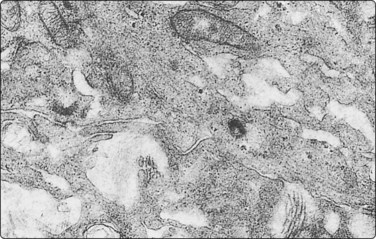

image

Fig. 11.20 Malignant islet cell tumor

Poorly cohesive cells of endocrine appearance; no obvious cytologic features to suggest malignancy. This tumor metastasized to the liver (MGG, HP).

These functional or nonfunctioning tumors of adults are situated mainly in the body and tail of the pancreas. The tumors are well within the scope of EUS cytodiagnosis.114,115 The neoplastic cells are mainly dissociated, but often form loose acinar or follicular clusters and curved or circular rows (Fig. 11.18). In the majority of cases, nuclei are characteristically round to oval and uniformly small. Occasionally, nuclear anisokaryosis may be prominent, but the nuclear chromatin pattern varies little between cells. The chromatin is evenly distributed, coarsely granular or ‘speckled’. The small nucleoli are not easily seen in Giemsa-stained smears. Due to its fragility, the cytoplasm is often dispersed in the background. When it is preserved, nuclei are eccentrically situated within defined cell borders. A very fine, red granularity is often discernible in MGG smears with high magnification. Clumps of amyloid may occasionally be seen, but necrosis is not observed.113,116-119 The cytological pattern of most islet cell tumors is sufficiently characteristic to be easily distinguished from that of pancreatic adenocarcinoma. Production and secretion of specific hormone products cannot be distinguished on the basis of routine cytological smears alone. If the secretory products of the neoplastic cells can be identified by immunocytochemical methods, a more specific diagnosis can be made with confidence. General neuroendocrine markers will usually be positive, such as neuron-specific enolase, synaptophysin, chromogranin-A, PGP9.5 and CD56. Specific secretory products, e.g. insulin can be marked by appropriate antibodies but this does not necessarily correlate with raised serum levels. Electron microscopy will demonstrate dense-core neurosecretory granules. A decision on whether a tumor is benign or malignant is problematic. Even histopathology is poorly predictive of aggressive behavior. In general, nuclear atypia and pleomorphism cannot be relied on as cytological criteria of malignancy (Fig. 11.20). More aggressive behavior correlates with a raised proliferation index assessed using Ki-67 immunohistochemistry (> 2%).120 This is a parameter in the WHO 2004 histology based-grading system.121,122 Only documentation of metastasis finally provides proof of malignancy.123,124